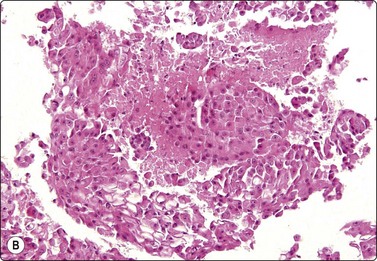

image image

Fig. 4.18 Chordoma

Physalipherous cells embedded in chondromyxoid stroma. The characteristic vacuolated cytoplasm and the chondromyxoid stroma are much less obvious in the Pap-stained smear. This tumor presented clinically as a retropharyngeal mass (A, MGG, HP; B, Pap, HP).

Chordoma may present as an orbital, nasal or posterior pharyngeal mass accessible to FNB through the oral cavity (Fig. 4.18). Of bone tumors affecting the skull, eosinophilic granuloma, multiple myeloma and metastatic carcinoma lend themselves to cytological diagnosis. Cytomorphological criteria for bone tumors are given in Chapter 16.